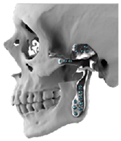

| 1 | 71 | FT-M0 | ![]() | Temporal bone, aygomatic arch, glenoid fossa and condyle | Unalloyed titanium mesh temporal and zygomatic backing capping the UHMWPE fossa | Cobalt-chromiun-molybdenum alloy condylar head and Titanium alloy body | Skull component: 62.0 mm titanium screws. Manibular component: 82.7 mm titanium screws |

| 2 | 58 | FA-M0 | ![]() | Glenoid fossa with medial extension and condyle | Alloyed titanium backing capping the UHMWPE fossa | Cobalt-chromiun-molybdenum alloy condylar head and Titanium alloy body | Skull component: 52.0 mm titanium screws. Manibular component: 82.7 mm titanium screws |

| 3 | 41 | FO-M3 * | ![]() | Glenoid fossa and complete left hemimandible | Alloyed titanium backing capping the UHMWPE fossa | Cobalt-chromiun-molybdenum alloy condylar head and Titanium alloy body consisting of two interloching pieces | Skull component: 52.0 mm titanium screws. Manibular component: 112.7 mm titanium screws |

| 4 | 71 | FA-M3 | ![]() | Left zygomatic arch, glenoid fossa and complete left hemimandible extended to the right hemimandible ramus | Alloyed titanium zygomatic backing capping the UHMWPE fossa | Titantium alloy | Skull component: 82.3 mm titanium screws. Manibular component: 62.7 mm titanium screws |

| 5 | 26 | FA-M0 | ![]() | Temporal bone, zygomatic arch, glenoid fossa and condyle bilatreally | Alloyed titanium zygomatic backing capping the UHMWPE fossa | Cobalt-chromiun-molybdenum alloy condylar head and Titanium alloy body | Skull component: 172.0 mm titanium screws. Manibular component: 192.7 mm titanium screws |

| 6 | 54 | F0-M2 | ![]() | Glenoid fossa and complete right hemimandible | Alloyed titanium backing capping the UHMWPE fossa | Cobalt-chromiun-molybdenum alloy condylar head and Titanium alloy mesh body | Skull component: 52.3 mm titanium screws. Manibular component: 92.7 mm titanium screws |

| 7 | 63 | F0-M3 | ![]() | Glenoid fossa and complete left hemimandible | Alloyed titanium backing capping the UHMWPE fossa | Cobalt-chromiun-molybdenum alloy | Skull component: 52.3 mm titanium screws. Manibular component: 82.7 mm titanium screws |

| 8 | 24 | F0-M3 * | ![]() | Glenoid fossa and complete right hemimandible extended to the left hemimandible ramus | Cobalt-chromium-molybdenum alloy backing capping the UHMWPE fossa | Cobalt-chromiun-molybdenum alloy | Skull component: 52.3 mm titanium screws. Manibular component: 112.7 mm titanium screws |

| 9 | 52 | FT-M0 | ![]() | Temporal bone, zygomatic arch, glenoid fossa extended medially and condyle | Cobalt-chromium-molybdenum alloy backing capping the UHMWPE fossa | Cobalt-chromiun-molybdenum alloy | Skull component: 82.3 mm titanium screws. Manibular component: 82.7 mm titanium screws |